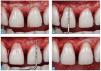

El método extremadamente respetuoso para obtener el espacio libre necesario para la carilla cerámica empieza en la zona proximal. Se aplica una punta de diamante larga y puntiaguda en paralelo al eje longitudinal del diente y a continuación se dirige en dirección al borde proximal. Mediante este procedimiento se rectifican cuidadosamente las zonas retentivas, lo cual facilita la colocación de la futura restauración (fig. 13). En el siguiente paso se procede a la reducción incisal en 1,5 mm sobre la base del encerado. Dado que no existe alargamiento del borde incisal, se realizó una preparación mínima, a fin de conservar la mayor cantidad posible de estructura del esmalte (fig. 14).

Fig. 13 a La preparación proximal mediante una fresa diamantada cónica. Sólo las zonas retentivas de los dientes se nivelan cuidadosamente, a fin de posibilitar la colocación de la futura restauración. b a d Los incisivos superiores tras la reducción proximal.

Figs. 14a y 14b. La reducción incisal.